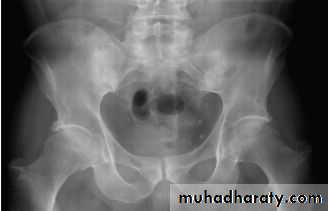

In established AS, radiographs of the sacroiliac joint show irregularity and loss of cortical margins, widening of the joint space and subsequently sclerosis, joint space narrowing and fusion.

Erosive changes may be seen in the symphysis pubis, the ischial tuberosities and peripheral joints.